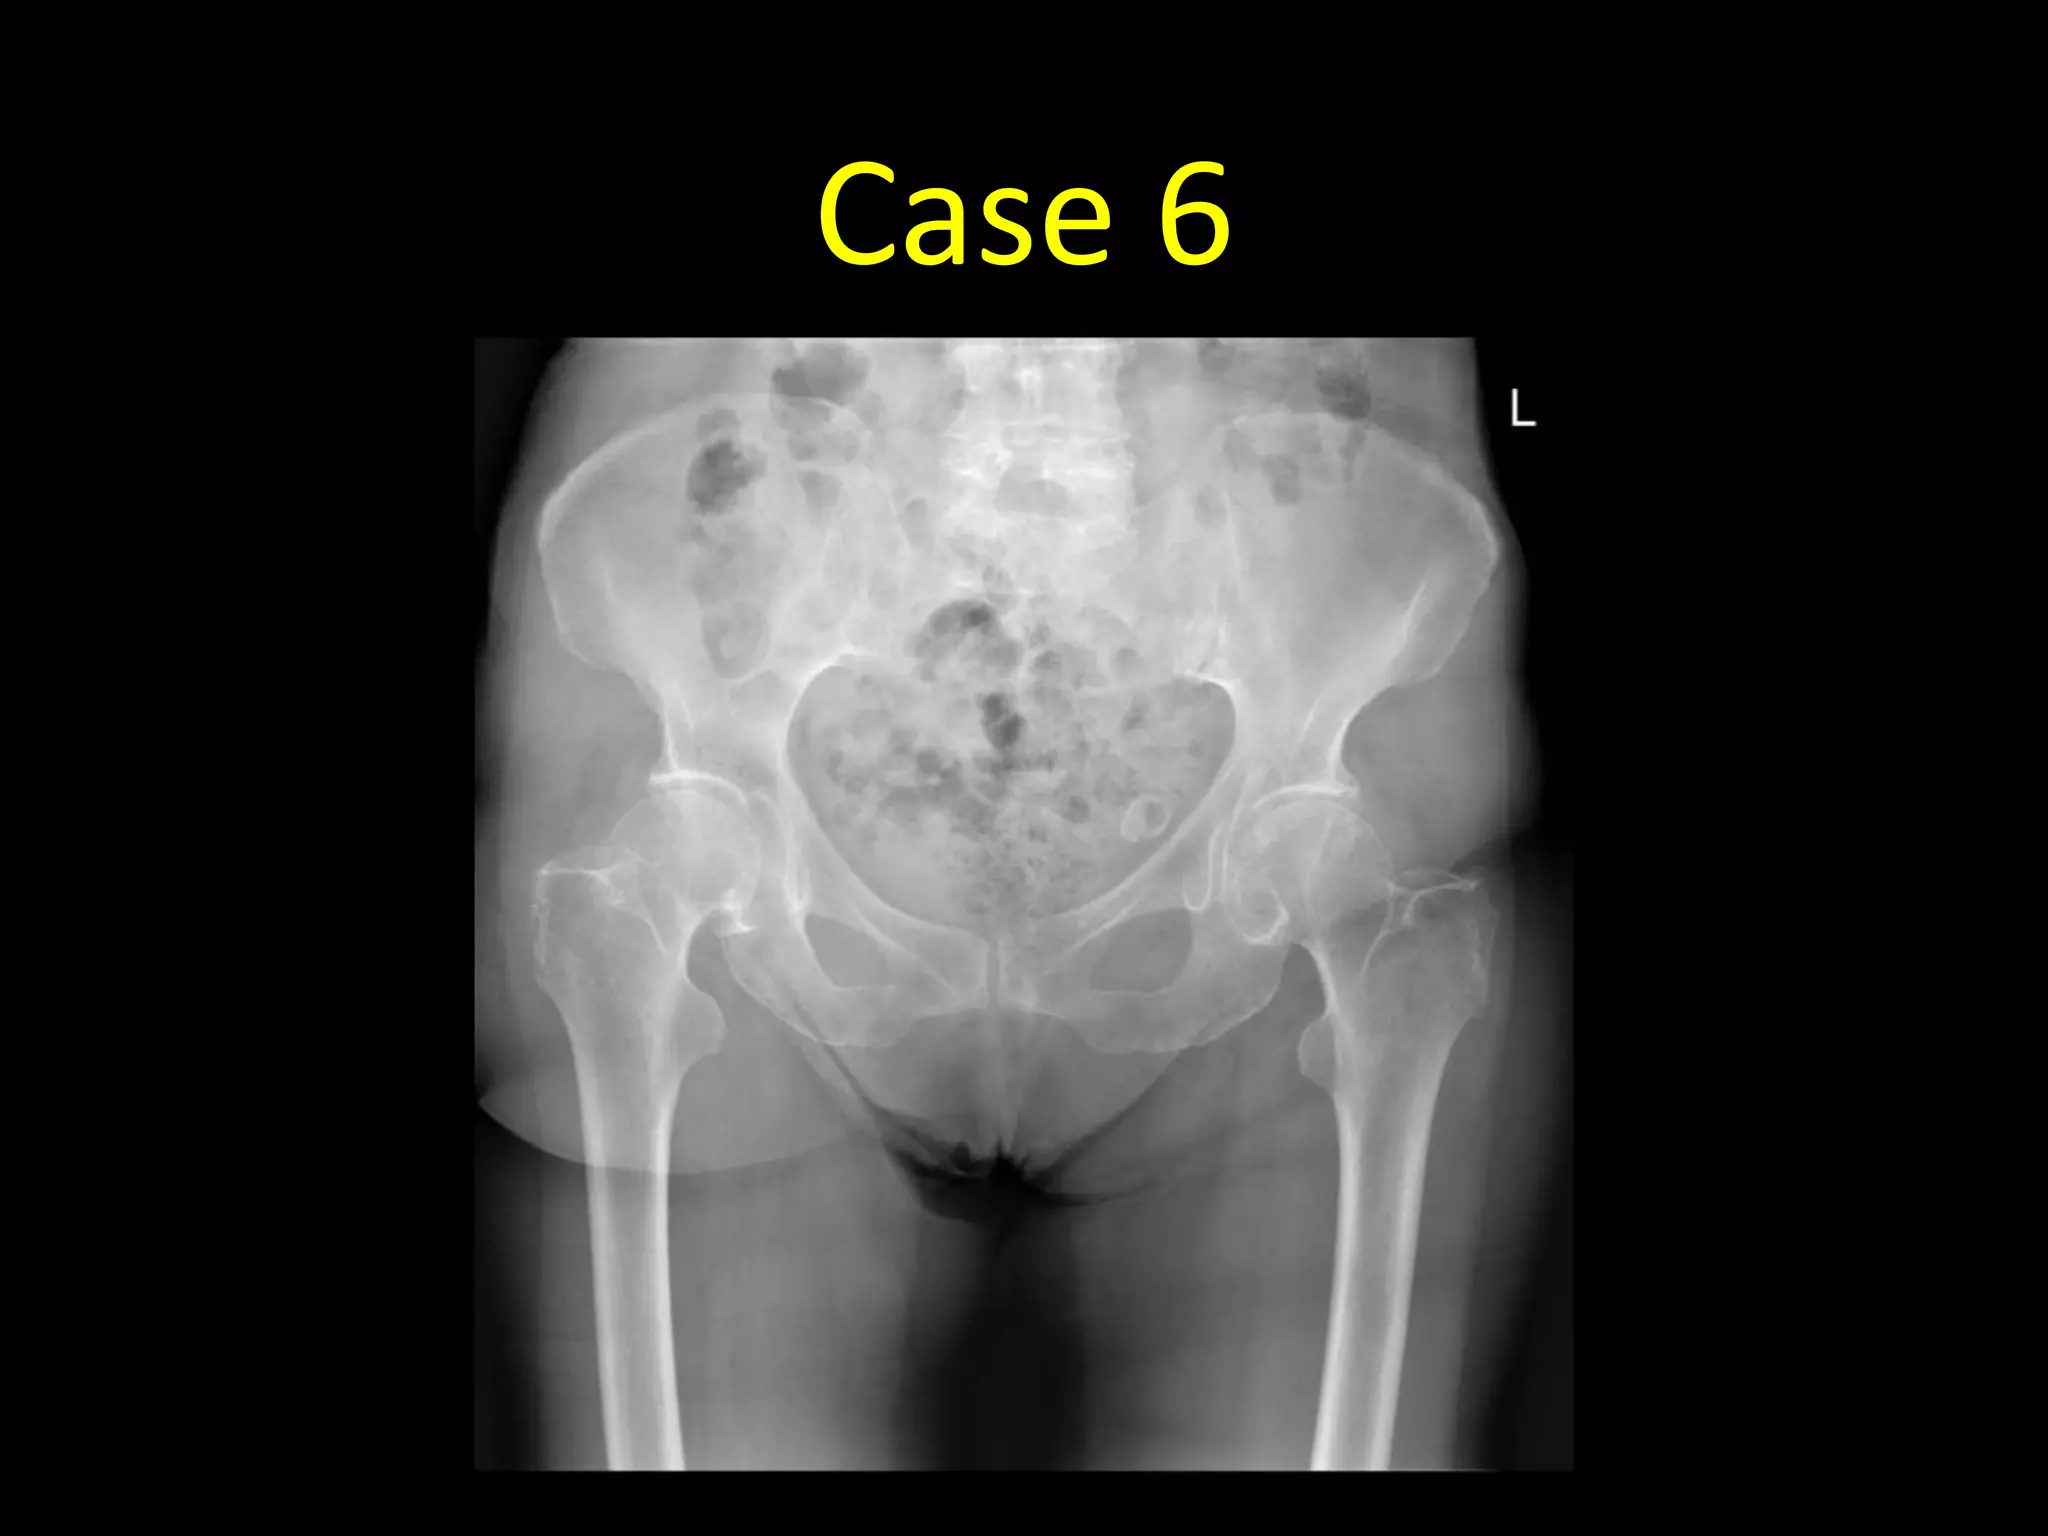

Case 6

• 87 year old with pain in the hip after a fall out of bed

• AP radiograph of the pelvis in

an 86 year old female

• There is a linear non-

displaced fracture of the right

femoral neck